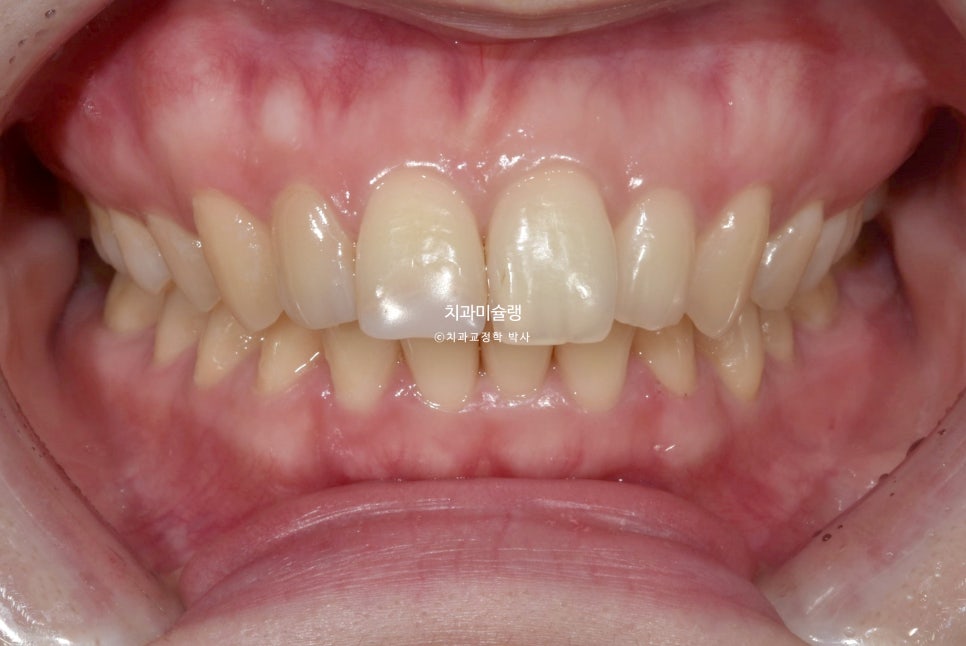

23년 4월, 교정치료를 위해 오신 20대후반 환자입니다. 실제론 앞니가 전반적으로 작은편임에도 불구하고 사진에서 앞니가 유독 커보이는건 돌출되어있기 때문입니다.

치열은 정면에서 볼때 원근법을 따르기에 튀어나와있으면 커보이고 뒤로갈수록 작아보이죠.

예전에 앞니를 다쳐서 부러진적이 있어 레진으로 치료해놓은 상태입니다.

앞니 2개가 유난히 돌출되어 있습니다.

앞니뿐 아니라 어금니 교합관계가 2급입니다.